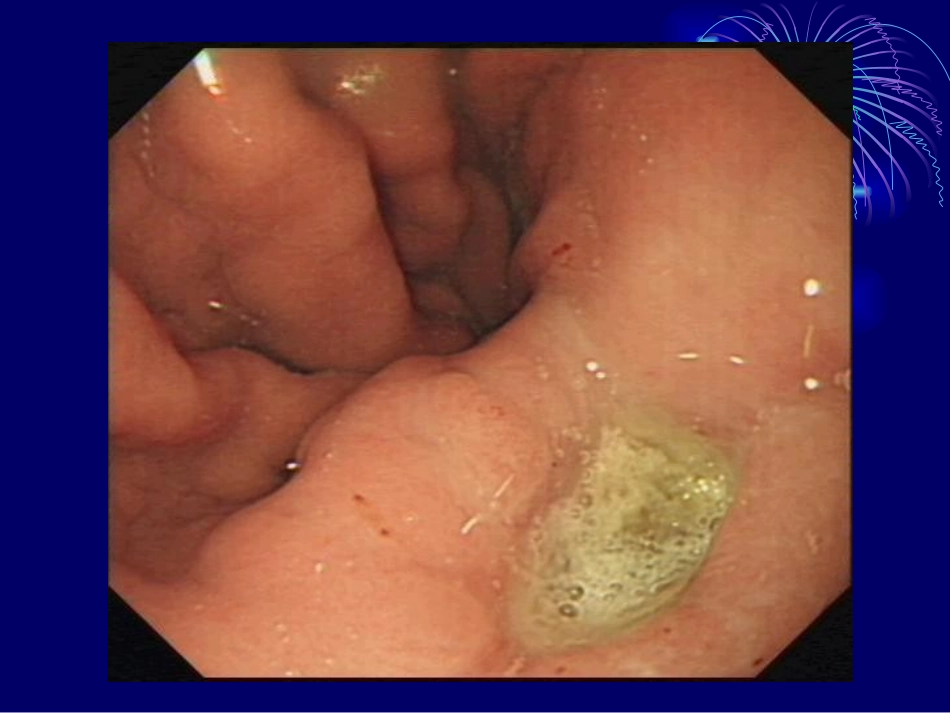

消化性溃疡的发病机制及治疗现状后前发病机制损害因素•胃酸胃蛋白酶•Hp感染•药物(阿司匹林,NSAID)•乙醇•胆盐防御因素•黏液屏障•碳酸氢盐•细胞再生•前列腺素和表皮生长因子•黏膜血流差别•胃溃疡:主要是防御因素或修复因素的削弱•十二指肠溃疡:主要是损害因素的增强目前共识①消化性溃疡是多种病因所致的异质性疾病群②抗酸药和抑酸药对溃疡的有效治疗作用证实了胃酸在溃疡病发生中的重要作用③根除Hp可显著降低复发率,证明Hp在溃疡的发生,特别在溃疡复发中起重要作用现代理念①没有胃酸就没有溃疡②没有Hp就没有溃疡复发③黏膜屏障健康就不会形成溃疡一胃酸和胃蛋白酶在消化性溃疡发病中仍起主导作用1.胃酸:消化性溃疡的定义源于溃疡的发生与胃酸胃蛋白酶的自身消化有关.“无酸无溃疡”理念至今仍沿用不衰.2.胃蛋白酶:对胃黏膜有侵袭作用,酸加胃蛋白酶比单纯酸更容易形成溃疡.胃蛋白酶的作用与酸密切相关,其生物活性取决于胃液ph值.二HP的发现使消化性溃疡病因学和治疗学发生了重大变革1.Hp是消化性溃疡的主要病因已达成共识:(1)Hp在消化性溃疡患者中有极高的检出率,胃溃疡在70%以上,十二指肠溃疡在90%-100%.(2)大量临床研究表明,根除Hp可加速溃疡愈合,显著降低溃疡复发率.传统的抑酸治疗只能使溃疡“愈合”,只能实现近期治疗目标,屡治屡发.而根除Hp则彻底改变溃疡病的自然病程,达到远期“治愈”目标.(3)Hp感染→慢性胃炎→溃疡(4)消化性溃疡只与某些特异的Hp菌株相关,与Hp的空泡细胞毒素A(vacA)和细胞毒素相关基因A(cagA)等有关.2.Hp感染对胃酸分泌和调节的影响:(1)Hp感染引起高胃泌素血症(血氨\炎性介质).(2)Hp感染可致D细胞分泌生长抑素减少→胃泌素↑.根除HP后,生长抑素恢复正常.3.Hp致消化性溃疡的发病机制:(1)目前认为Hp的致病机制包括:Hp的毒素引起胃黏膜的损害;宿主的免疫应答介导胃黏膜损伤;Hp感染致胃酸分泌和调节异常.HP致病因子:(a)与定植有关的致病因子(鞭毛,尿素酶,黏附因子);(b)以损伤胃黏膜为主的致病因子(vacA,cagA,溶血素,脂多糖,尿素酶,脂酶,蛋白酶);(c)与炎症和免疫有关的致病因子(脂多糖,cagA,尿素酶,热休克蛋白,趋化因子);(d)其他致病因子(过氧化氢酶,过氧化物歧化酶,离子结合蛋白等)(2)HP致消化性溃疡的五种学说:漏屋顶学说:有炎症的胃黏膜好比漏雨的屋顶,无胃酸(雨)就无溃疡.抑酸治疗,溃疡愈合,但根除Hp,则溃疡不易复发.胃泌素-胃酸学说:Hp→胃窦PH↑→胃泌素↑-胃酸增加-溃疡.胃上皮化生学说:Hp定植在十二指肠内的胃化生上皮,引起黏膜损害,导致十二指肠溃疡形成.介质冲洗学说:Hp感染导致多种炎性介质释放,随着胃排空进入十二指肠,导致黏膜损伤.免疫损伤学说:Hp通过免疫损伤机制导致溃疡形成.但任何一种学说都只能从不同角度阐明机制的某一部分,不能解释溃疡病发病的全部机制.三黏膜屏障的损害是溃疡病发病的基本原因胃黏膜屏障:黏液和碳酸氢盐的分泌胃上皮细胞间的紧密连接脂蛋白层胃黏膜血流和细胞的更新能损害胃黏膜的药物:NSAID肾上腺皮质激素某些抗生素抗癌药等NSAID损害胃黏膜的机制:(1)NSAID多系脂溶性药物,能直接穿过胃黏膜屏障导致H离子反弥散,造成黏膜损伤.(2)抑制前列腺素合成,削弱黏膜保护机制.四遗传因素在消化性溃疡发病中的作用仍应肯定1.溃疡病患者家族的高发病率:十二指肠溃疡患者的子女溃疡患病率较无溃疡患者的子女高3倍,单卵双胎发生溃疡的一致性高达53%,双卵双胎发病的一致性达36%.胃溃疡患者的子女易患胃溃疡,十二指肠溃疡患者的子女易患十二指肠溃疡,提示这两种病是两种不同基因遗传性疾病.2.消化性溃疡与血型的关系:O型血者溃疡发生率高于其他血型.3.消化性溃疡与人类白细胞抗原(HLA)的关系:HLA-B5,HLA-B12,HLA-BW35型人群易患十二指肠溃疡.五胃和十二指肠运动功能异常是消化性溃疡发病中的新课题1.胃排空和胃酸分泌:正常情况下胃排空随十二指肠内PH下降而减慢,而十二指肠溃疡患者酸负荷超过正常人,但其排空速度反比正常人快,原因不明.2.胃排空延迟和胆汁反流:胃溃疡时多有排空延迟,同时又促进了胆汁反流,...

消化性溃疡的发病机制及治疗现状